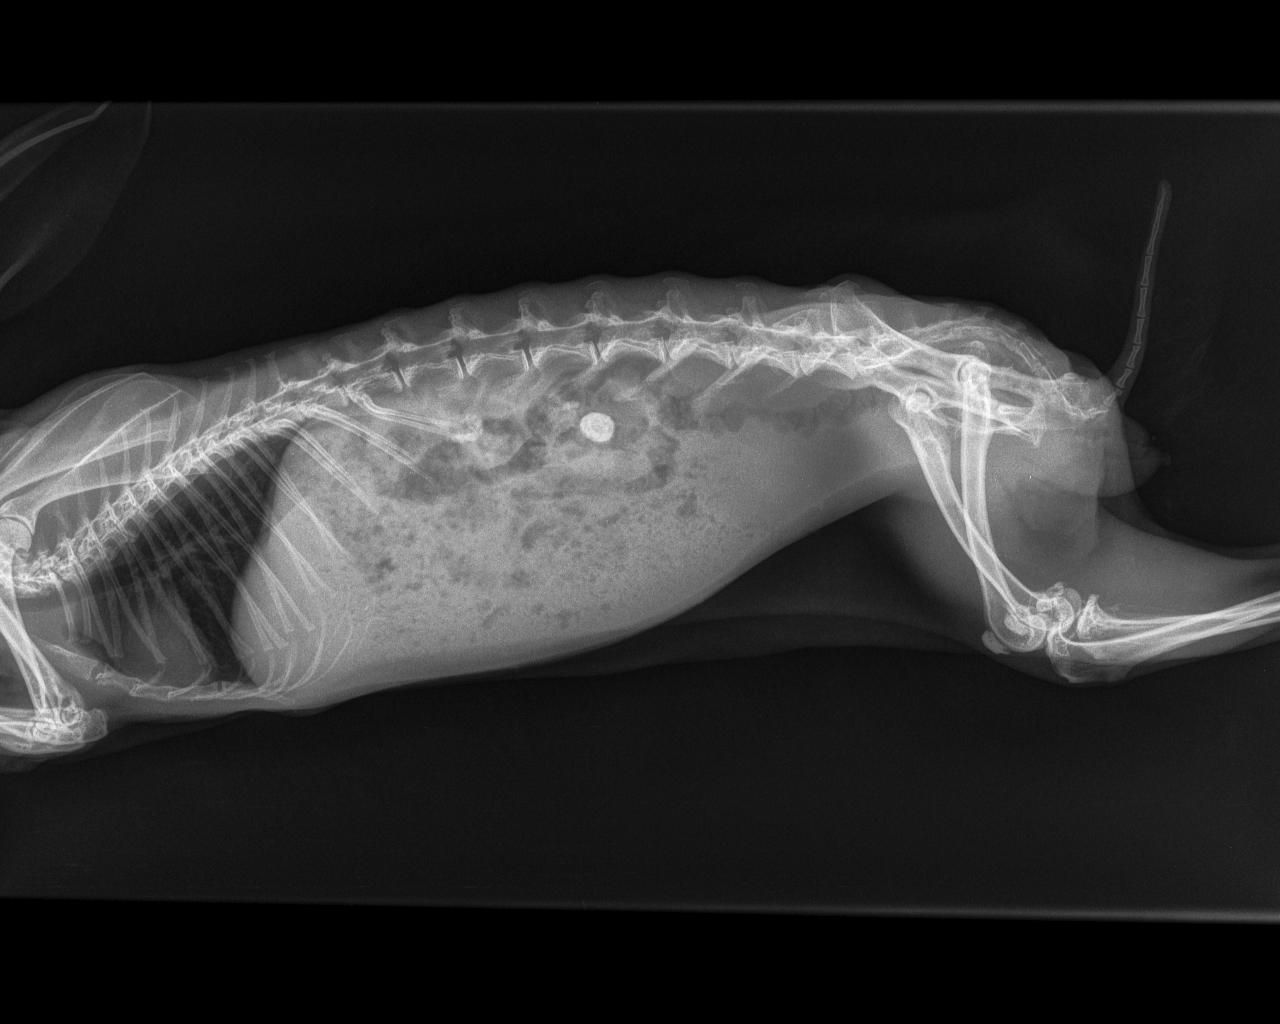

Tumeur utérine des lapins

Les tumeurs utérines sont particulièrement fréquentes chez les lapines au-delà de l'âge de 3 ans. C'est la raison pour laquelle il est fortement recommandé de stériliser préventivement toute les lapines pour prolonger leur durée de vie.

Les lapines peuvent présenter de l'abattement et des pertes de sang (parfois spectaculaires). Elles présentent parfois des grossesses nerveuses (pseudogestation) associées au développement de la tumeur utérine. Le diagnostic se fait par échographie, d'une part pour confirmer la présence de la tumeur mais aussi pour faire un bilan d'extension et vérifier l'absence de métastases abdominales sur le foie ou la paroi abdominale. En cas de confirmation de tumeur, une radiographie thoracique doit systématiquement être proposée pour rechercher des métastases pulmonaires.

Le traitement de choix est la chirurgie de stérilisation (ovariohystérectomie). Quand elle est pratiquée à temps, elle est d'excellent pronostic. En cas de métastases des options de chimiothérapie peuvent être proposées.